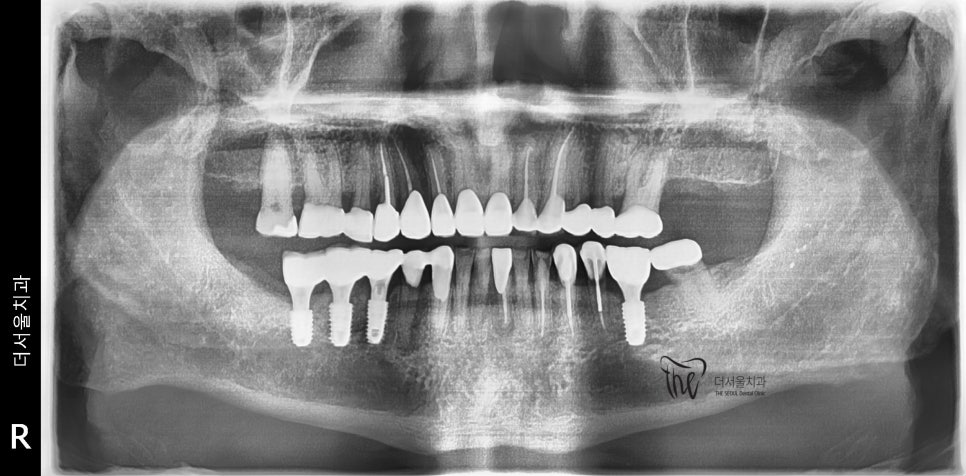

우선 교합면에서 바라보게 되면,

곳곳에 치아 결손 부위가 관찰이 되는데

이가 빠진지 시간이 꽤나 오래 되셨다는 것을

한 눈에 알아차릴 수 있습니다.

바로 결손부위를 보게 되면, 골 폭이 상당히

좁아져 있는 것을 볼 수 있는데 이는 치아 상실 후

방치 된 시간이 꽤나 오래 되었다는 것에 따른

반증이기 때문입니다.

그리고, 임플란트 수술 을 했던 곳은

뼈가 아무는데 대략 2개월 가량이 필요하니

그 이후에, 시간 나실 때 다시 또 한국으로 오셔서

지르코니아 크라운을 올리면 된다 라는

안내를 드렸습니다.

『10개월 뒤…』

개인사도 있었으며, 코로나 이슈에 따라서

10개월 가량 한국으로 못 들어오셨다 말씀을

하셨었습니다. 그때까진 임시치아로 버텨오셨는데

그리고, 지르코니아 크라운을 연결해드리면서

결손부위에 따른 재건은 모두 마쳐드렸습니다.